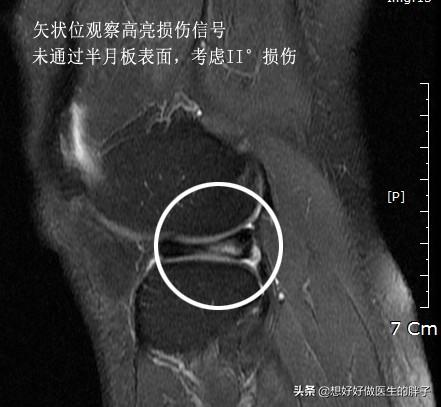

而前角内见线性高信号影就说明为I-II°半月板损伤,因为损伤信号没有到达关节面,损伤是在半月板内部的,镜下很可能看见的是正常的半月板,下面是半月板II°损伤的核磁和镜下所见,和III°损伤有天壤之别。

我相信经过我的解读应该明白了半月板II°与III°撕裂的巨大区别。一般III°撕裂我们建议手术治疗,而II°撕裂保守即可。